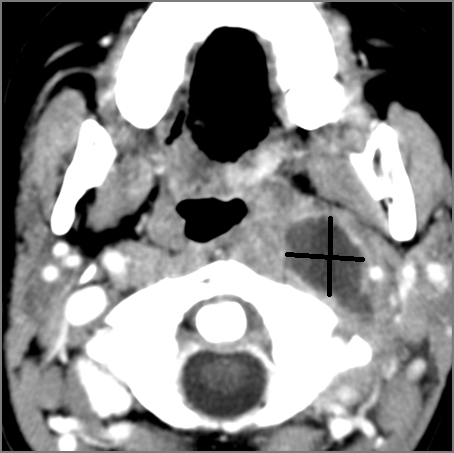

There is edema within the adjacent deep neck, retropharyngeal and/or prevertebral spaces

There is abscess within the adjacent deep neck, retropharyngeal and/or prevertebral spaces.